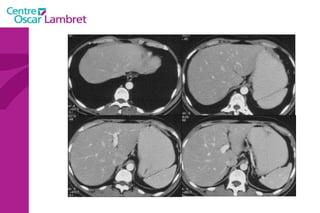

L’appareil urinaire L’appareil urinaire se compose des reins, des uretères et de la vessie. Les reins  sont rétro-péritonéaux : de part et d’autre du rachis entre T12 et L3. Fixés sous les côtes, ils sont en liaison avec l’artère rénale . Le rein possède une fonction secrétoire puis excrétoire à partir du pyelon, origine de l’uretère.

L’appareil urinaire

L’appareil urinaire Les uretères  se dirigent vers le bas, en avant et en dedans pour rejoindre la partie postéro supérieure de la vessie. On distingue 3 parties : L’uretère lombaire (12 cm) L’uretère iliaque (3 cm) L’uretère pelvienne (12 cm)

La vessie  : Elle recueille l’urine qui lui parvient par les uretères. L’urine est évacuée par l’urètre lors de la miction. L’appareil urinaire

Les surrénales  sont 2 glandes endocrines triangulaires situées au dessus des reins. Elles sont principalement responsables de la gestion des situations de stress via la synthèse de corticostéroïdes et de cathécolamines, entre autres le cortisol et l‘adrénaline.  Intérêt d’un balisage digestif pour l’étude de ces glandes L’appareil urinaire